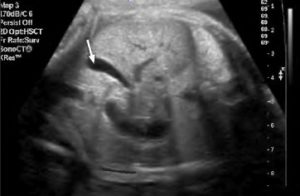

Патологические состояния данного типа возникают при наличии дивертикулов, изгибах и перекрутов тела и/или шейки желчного пузыря, что приводит к его деформации. Самым точным методом диагностики является ультразвуковое исследование. Если аномалия возникает из-за перекрута, происходит нарушение продольной оси. В этом случае орган принимает форму улитки, все его части фиксируются к 12-перстной кишке. Возможно его крепление к поперечному отделу ободочной кишки. Перекруты могут быть функциональными и структурными. В первом случае проблема решается самостоятельно, а во втором — терапевтическим путем. Если аномалия возникла из-за излишнего натяжения, наблюдается сужение пузырного тела по всей окружности или частично. Врожденная аномалия возникает из-за непропорционального роста органа и его ложа. Этот тип деформаций приводит к нарушению прокачки желчи в системе, что вызывает застои. Длительные нарушения приводят к дистрофическим изменениям в стенках пузыря и снижению его сократительной способности. При генетических аномалиях форма органа остается неизменной. Если воспаление серозной оболочки стало причиной излишнего натяжения, орган может восстановить свою прямую форму. При наличии дивертикулов происходит выпячивание стенки пузыря в виде мешка из-за отсутствия эластичного каркаса. Развитие аномалии в желчном пузыре происходит на фоне его общей дисфункции. Патология проявляется сильными болями из-за застоя желчи и часто сопровождается воспалением и образованием камней. Другие формы, которые может принимать желчный пузырь, включают S-образную, бумеранговидную и шаровидную формы.

Ультразвуковое исследование (УЗИ) является наиболее точным методом диагностики патологических изменений в структуре и форме пищеварительного органа. Оно позволяет получить информацию о состоянии, структурных особенностях и функциональности стенок и протоков. УЗИ может быть общим или проводиться с нагрузкой, когда данные снимаются после употребления желчегонного завтрака пациентами. В случае нечеткой визуализации системы с протоками на УЗИ, пациентам назначают компьютерную томографию (КТ) и магнитно-резонансную томографию (МРТ).